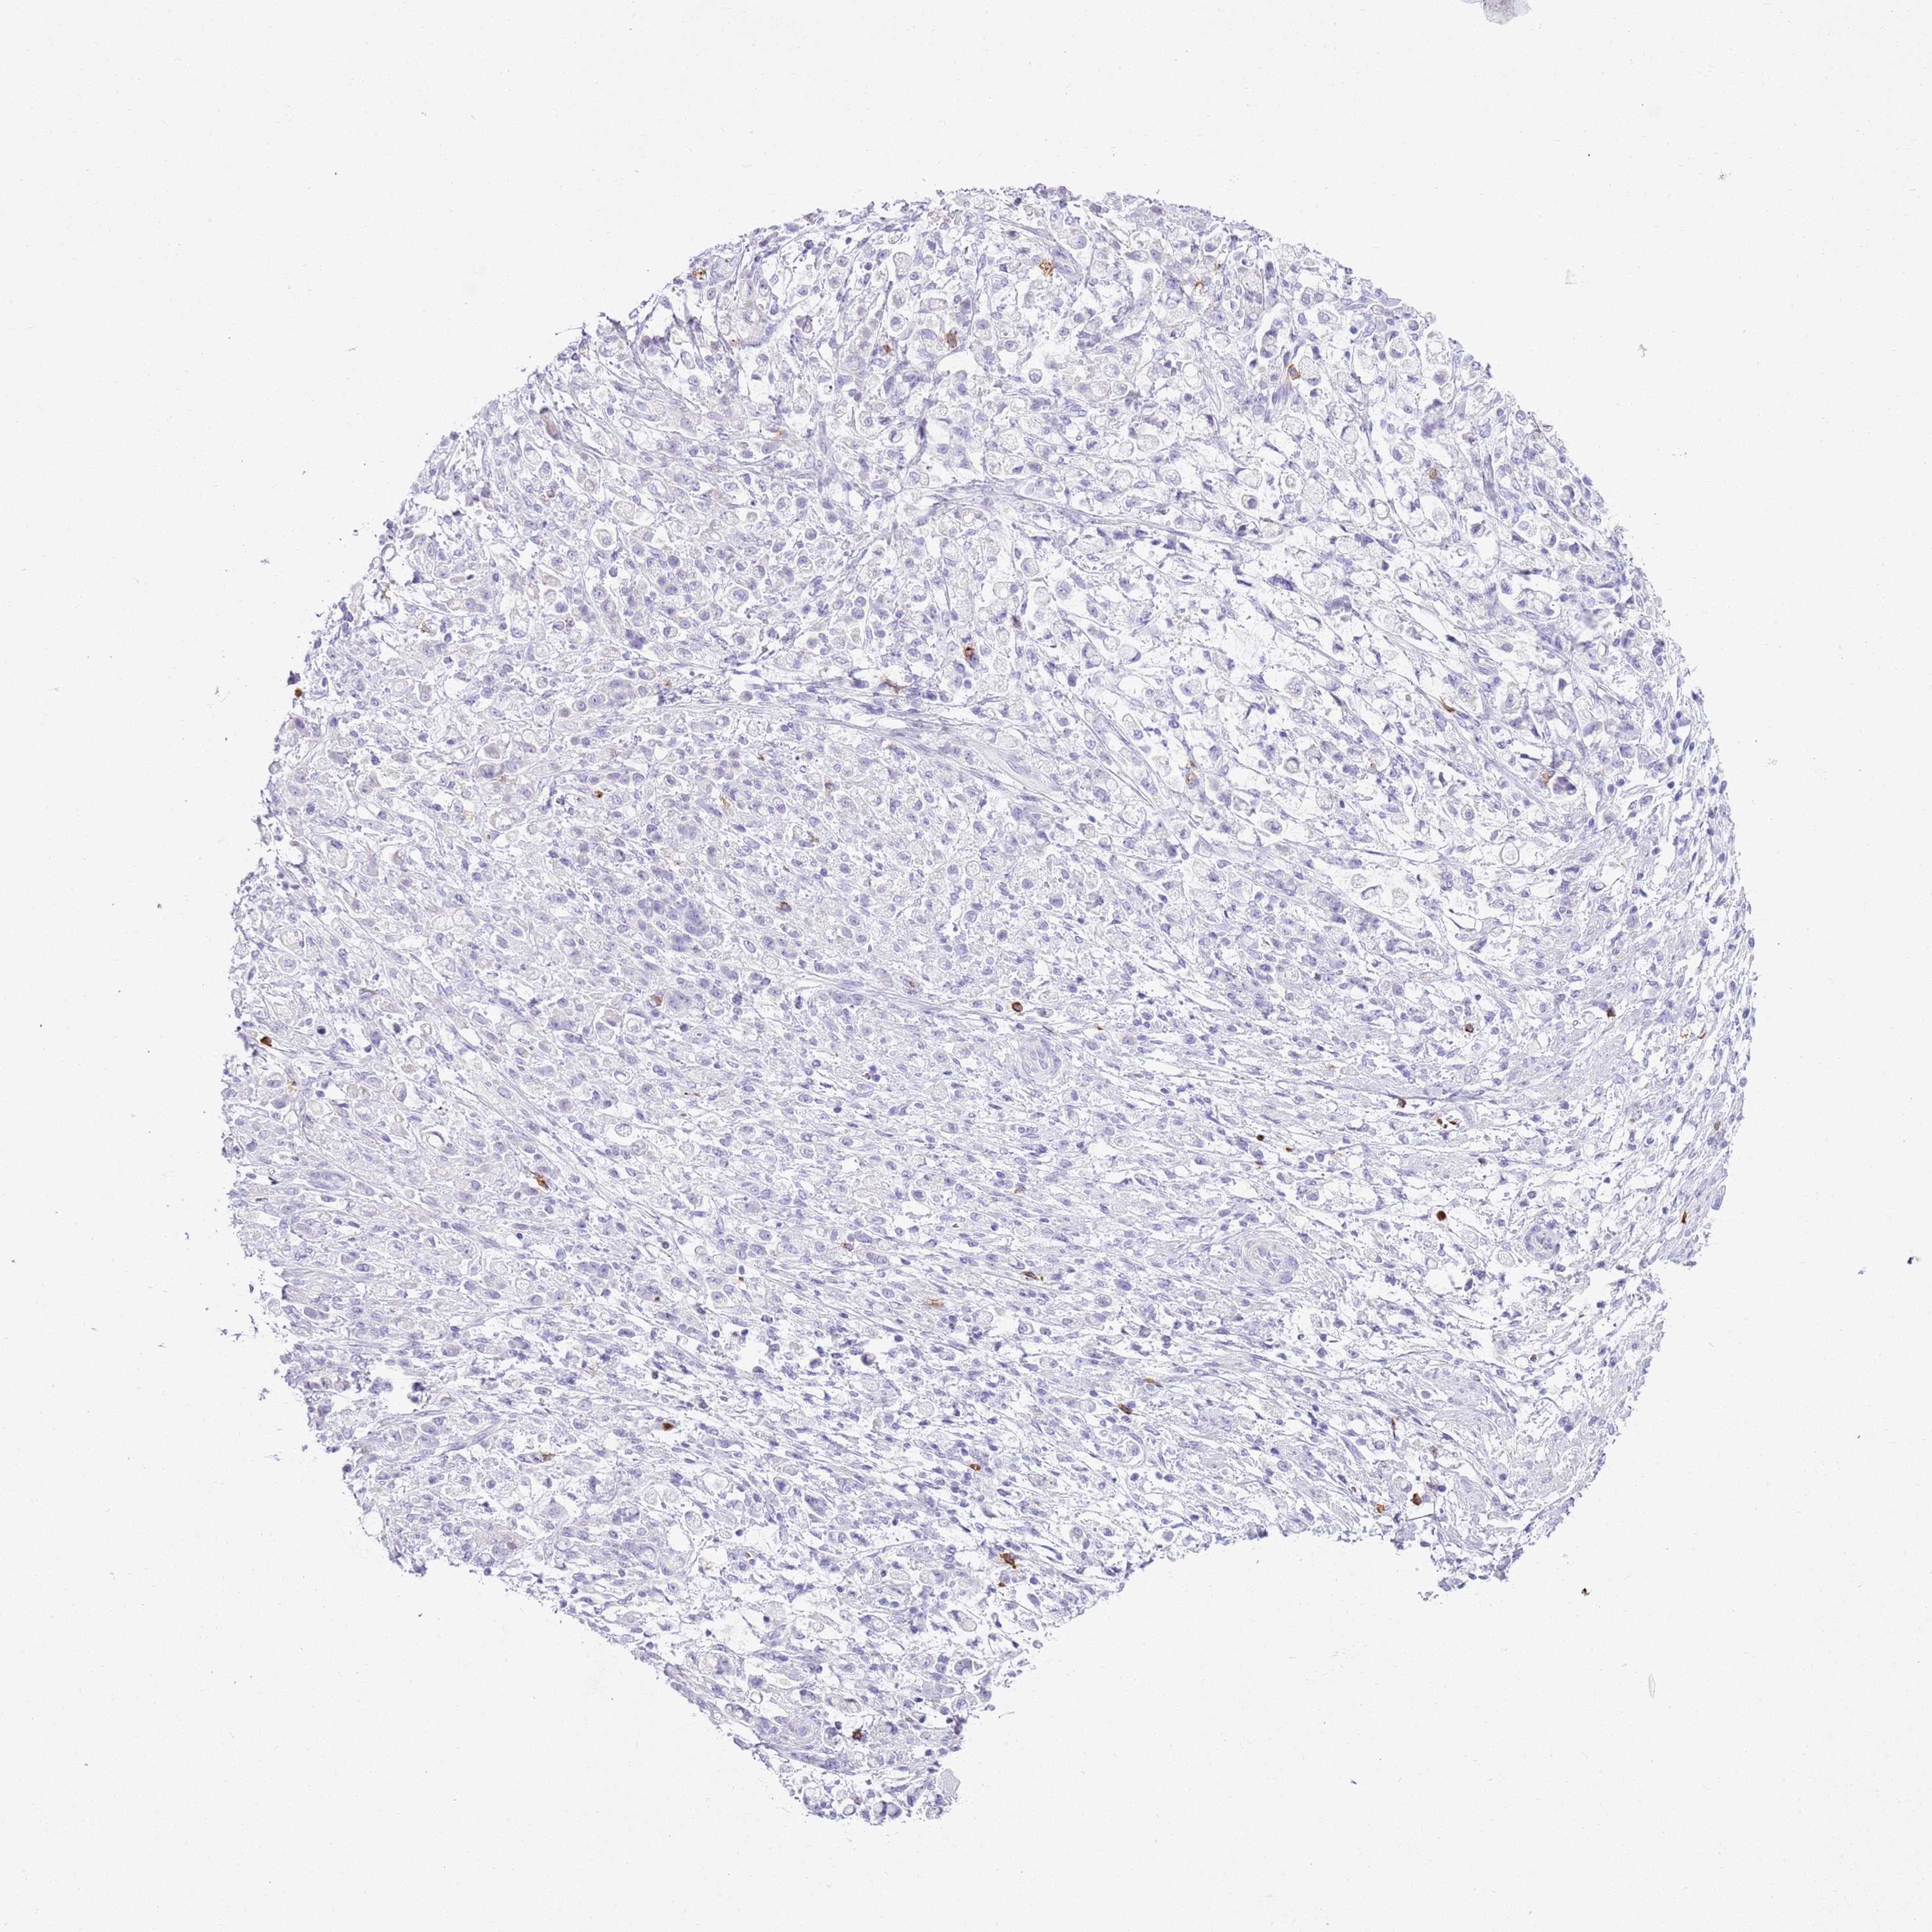

STOMACH CANCER - Protein expressioni

A mouse-over function shows sample information and annotation data. Click on an image to view it in a full screen mode. Samples can be filtered based on level of antibody staining by selecting one or several of the following categories: high, medium, low and not detected. The assay and annotation is described here.

Antibody stainingi

Antibody staining in the annotated cell types in the current human tissue is reported as not detected, low, medium, or high, based on conventional immunohistochemistry profiling in selected tissues. This score is based on the combination of the staining intensity and fraction of stained cells.

Each image is clickable and will lead to virtual microscopy that enables deeper exploration of all samples and also displays staining intensity scores, fraction scores and subcellular localization as well as patient and tissue information for each sample.

Antibody HPA041820

Antibody HPA046601

Antibody HPA077640

Staining

High

Medium

Low

Not detected

Intensity

Strong

Moderate

Weak

Negative

Quantity

>75%

75%-25%

<25%

None

Location

Nuclear

Cytoplasmic/membranous

Cytoplasmic/membranous,nuclear

Adenocarcinoma, NOS

Adenocarcinoma, High grade